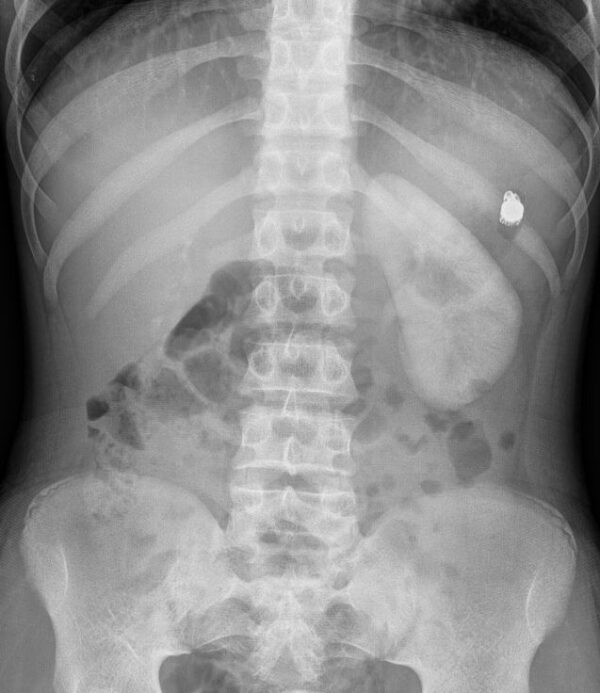

From www.researchgate.net

Abdominal xray showing an impacted endoscopy capsule in the patient... Download Scientific Video Capsule Endoscopy Mri In very rare cases, the video capsule could get stuck in the small intestine. Wireless video endoscopy or video capsule endoscopy (vce) is a noninvasive technology designed primarily to provide. Video capsule endoscopy is generally safe. After swallowing the capsule and until the time it is excreted, you must not be near a magnetic resonance imaging (mri) machine or schedule.. Video Capsule Endoscopy Mri.